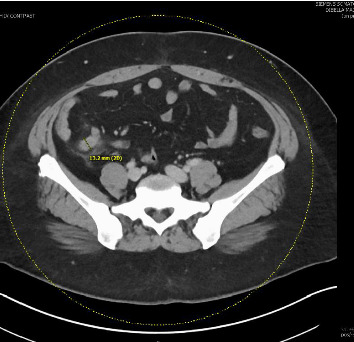

血吸虫病是一种由血吸虫引起的寄生虫病,常见于撒哈拉以南非洲以及亚洲和美洲的某些其他地区。该病可表现为各种急性和慢性疾病,很少表现为急性阑尾炎。在此,我们报告一例来自非流行地区(纽约市)的36岁女性患者,有旅行史,表现为继发于肠道血吸虫病的急性阑尾炎。

Schistosomiasis is a parasitic disease caused by blood flukes commonly found in sub-Saharan Africa and select other areas in Asia and the Americas. The disease can manifest in a wide range of acute and chronic conditions, rarely presenting as acute appendicitis. Herein we report a case of a 36-year-old female patient from a nonendemic area (New York City) with a history of travel presenting with acute appendicitis secondary to instestinal schistosomiasis.